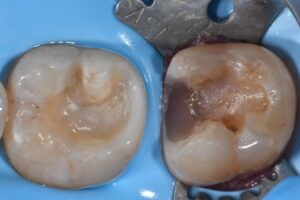

Direct complex restoration featuring peri-crestal caries

// Substrate Optimization using 29 micron Al2O3 particles #AquacareUK #VelopexUK